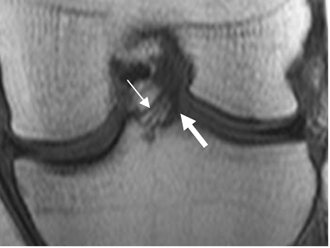

La orientación del LCA es uno de los signos con mayor sensibilidad y especificidad, de lesión ligamentaria.

Fig 13. LCA normal.

A: RM sagital en T1, B: RM sagital en T2 y C: RM sagital en FFE. Ligamento normal,

hipointenso en todas las secuencias.

Fig 14. LCA normal.

RM coronal en T1. Bandas normales del LCA. Anteromedial (Flecha delgada) y posterolateral (Flecha gruesa).

Fig 15. LCA normal.

A: RM sagital en T1. Relación normal, con el platillo tibial.

B: RM sagital en T2. Ruptura del LCA, el cual está horizontalizado y con disminución del ángulo.

Fig 16. LCA normal.

A: RM sagital en T1. Angulo normal de vértice superior, con la línea intercondilea.

B: RM sagital en T2. Ruptura del LCA, con ángulo de vértice inferior.